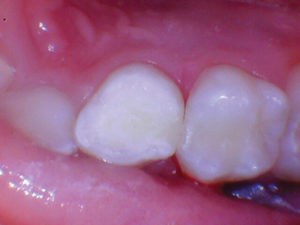

Caso 3

La caries recurrente en un diente primario que involucra múltiples superficies generalmente conduce a una cobertura total y con razón. Sabemos que los materiales a base de resina tienen fugas en ambientes hostiles ácidos y acribillados de sacarosa; por lo tanto, se recomienda una cobertura total en estos casos. ¿Qué pasaría si pudiéramos restaurar con un material más estético para los padres estéticos? En estos casos estéticos, todavía necesitamos resistencia y un material activo no inerte.

Figura 1. Fotografía preoperatoria del segundo molar primario superior derecho con caries distoocluso-bucal. En el pasado, al menos para mí, el tratamiento habría sido una corona de cobertura total (probablemente de acero inoxidable). Debido a las preocupaciones estéticas de los padres, es bueno tener una opción alternativa, especialmente un material que sea activo dentro del entorno oral. |

Figura 2. La caries se excavó y se eliminó todo el esmalte socavado. |